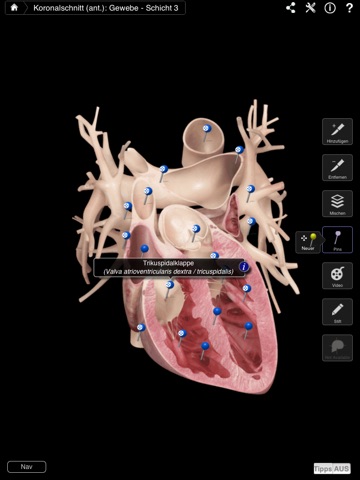

• Querschnitte lassen sich mit Gesten erstellen - für Ansichten in der Koronal-, Sagittal- oder Transversalachse - Popups führen Sie durch den Prozess.

• Skalpell-Funktion - Venen, Arterien und Gewebe lassen sich ein- oder ausblenden.

• Pins werden sowohl in Deutsch als auch in Latein angezeigt.

• Anpassbare Pins - Sie können eigene Pins und Anmerkungen erstellen oder Anmerkungen zu vorhandenen Pins hinzufügen.